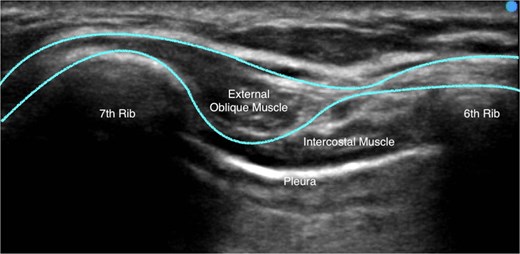

The EOI block was performed with patients in the supine position. The sixth rib was determined using the level of the xiphoid process at the midclavicular line. A Sonosite Edge II ultrasound machine (Fujifilm) was used, and a linear 15–4-MHz ultrasound transducer was positioned in the sagittal oblique plane, with the probe cranial end rotated slightly medially, at the sixth rib level between the anterior axillary and midclavicular lines. The subcutaneous tissue, external oblique muscle, ribs, intercostal muscles, pleura, and lungs were identified from superficial to deep, as seen in Fig. 1. With an in-plane technique, a 22-gauge Sonoplex® STIM single shot nerve block needle (PAJUNK®) was used to inject local anaesthetic between the fascial plane of the external oblique muscle and the external intercostal muscle at the level of the intercostal space between the sixth and seventh rib. A clear separation of the muscle plane between the external oblique muscle and the external intercostal muscle was observed upon the injection of the local anaesthetic, as demonstrated in Video 1.

A typical ultrasound image obtained while administering the EOI block. The external oblique muscle, intercostal muscles, sixth rib, seventh rib, and pleura is labelled. The border external oblique muscle border is outlined.